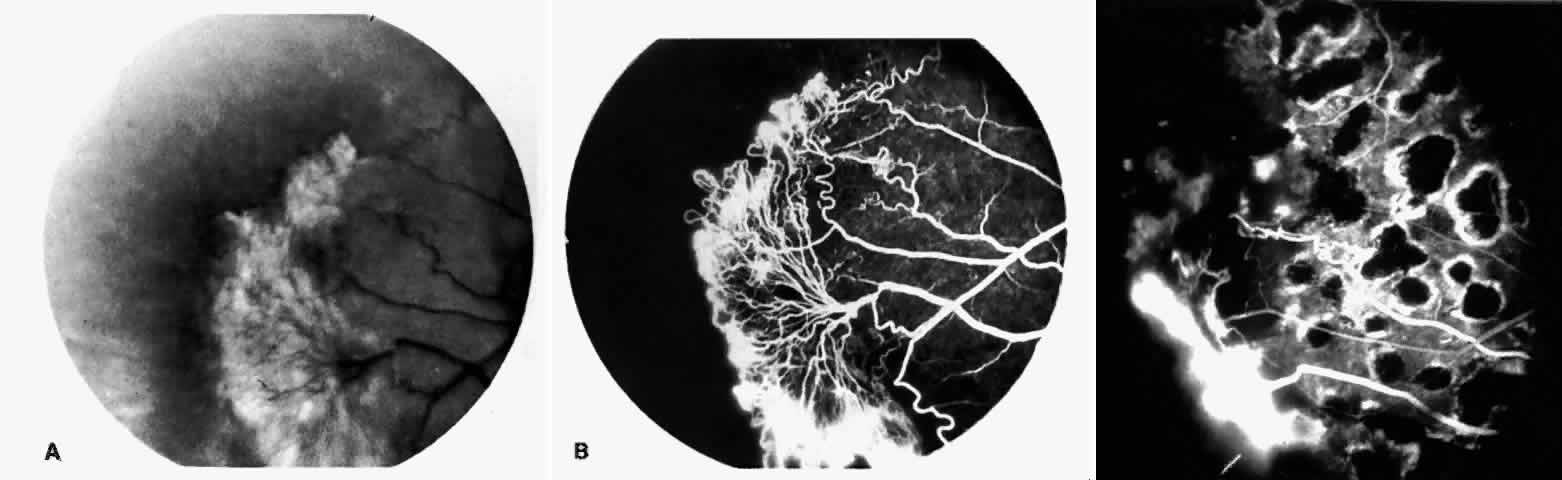

STAGE II: PERIPHERAL ARTERIOLAR-VENULAR ANASTOMOSES. Following occlusion of the terminal arterioles, anastomotic channels form to channel the blood from the occluded arteriole to the nearest venules. These anastomoses form at the interface between the perfused and nonperfused retina. Most likely, they are dilated preexisting capillaries rather than new vessels, since they do not leak on fluorescein angiography. The redirection of blood flow is probably due to hydrostatic forces (Figs. 22 and 23).

|

STAGE III: PRERETINAL NEOVASCULARIZATION (PROLIFERATIVE SICKLE RETINOPATHY). “Sea fan”-shaped neovascularization typically develops on the venular side of an arteriolar-venular anastomosis, mimicking the normal development of retinal capillaries (Fig. 24).125 A lowered oxygen tension and angiogenic factors released on the venular side may be the stimulus for neovascular growth.125,126 In most instances, the direction of growth is toward the ora serrata, from the perfused retina toward the nonperfused retina. Presumably, this represents an abortive attempt to revascularize the nonperfused retina, initiated by vasoproliferative factors.

The characteristic neovascular lesions of PSR are called sea fans because they resemble the marine invertebrate Gorgonia flabellum.70 They tend to occur more commonly in the temporal periphery, but they have been reported to occur in the temporal macula in the presence of extensive nonperfusion.130,133 Initially they grow on the surface of the retina, but they often become elevated into the vitreous and adhere to a partially detached posterior hyaloid.114 It may be difficult to visualize small sea fans ophthalmoscopically; however, fluorescein angiography clearly demonstrates leakage of dye into the vitreous (Fig. 25). The feeding arteriole is usually more tortuous than the draining venule (Fig. 26). Early on, the neovascular lesion is fed by a single arteriole and drained by a single venule, but with time, additional arterioles and venules become arborized within the lesion (Fig. 27).129 Growth of the sea fan often occurs circumferentially, rather than radiallyÜmh- 1Ý, toward the ora serrata. Progressive circumferential growth may lead to neovascular lesions extending around the entire periphery. As it matures, a white fibroglial mantle often covers the neovascular tissue (Color Plate 2B).